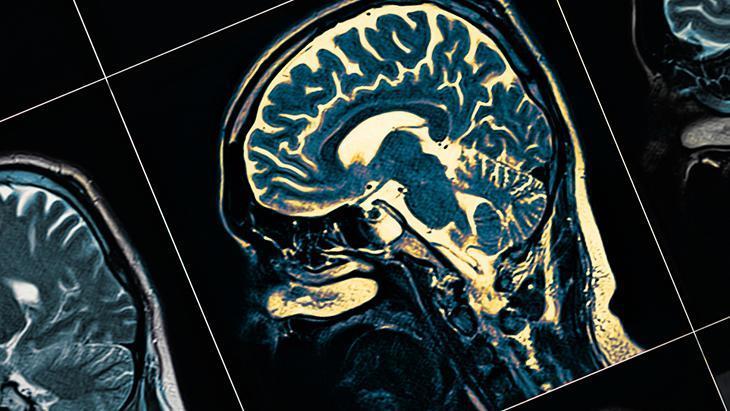

Toplumda ‘gençlerde unutkanlık arttı’ algısının büyük ölçüde demans dışı nedenlerle sağlık kuruluşlarına yapılan başvuruların artmasından ve tanı yöntemlerine daha erken ve kolay erişilmesinden kaynaklandığını belirten Nöroloji Uzmanı Prof. Dr. M. Zülküf Önal, manyetik rezonans görüntüleme olanaklarının yaygınlaşması, bilişsel tarama testlerinin artması ve hekim ile toplum farkındalığının yükselmesiyle birlikte daha fazla vakanın tanı aldığını, bunun da ‘demans genç yaşlara indi’ algısını güçlendirdiğini söyledi.

“Buna karşın sinsi başlangıçlı, aylar ya da yıllar içinde yavaş ama belirgin ilerleyen bir tablo; yeni bilgileri öğrenmede belirgin güçlük, aynı soruların tekrarı ve günlük yaşam işlevlerinde kayıp nörodejeneratif bir süreci akla getirmelidir. Genç yaşta ‘psödo demans’ sanılan tablo depresyon olabileceği gibi tam tersi şekilde depresyon ya da kişilik değişimi olarak etiketlenen bir demans tablosu da gözden kaçabilir. Bu nedenle hasta yakını gözlemleri, nöropsikolojik testler ve beyin MR ile değerlendirme önemlidir”